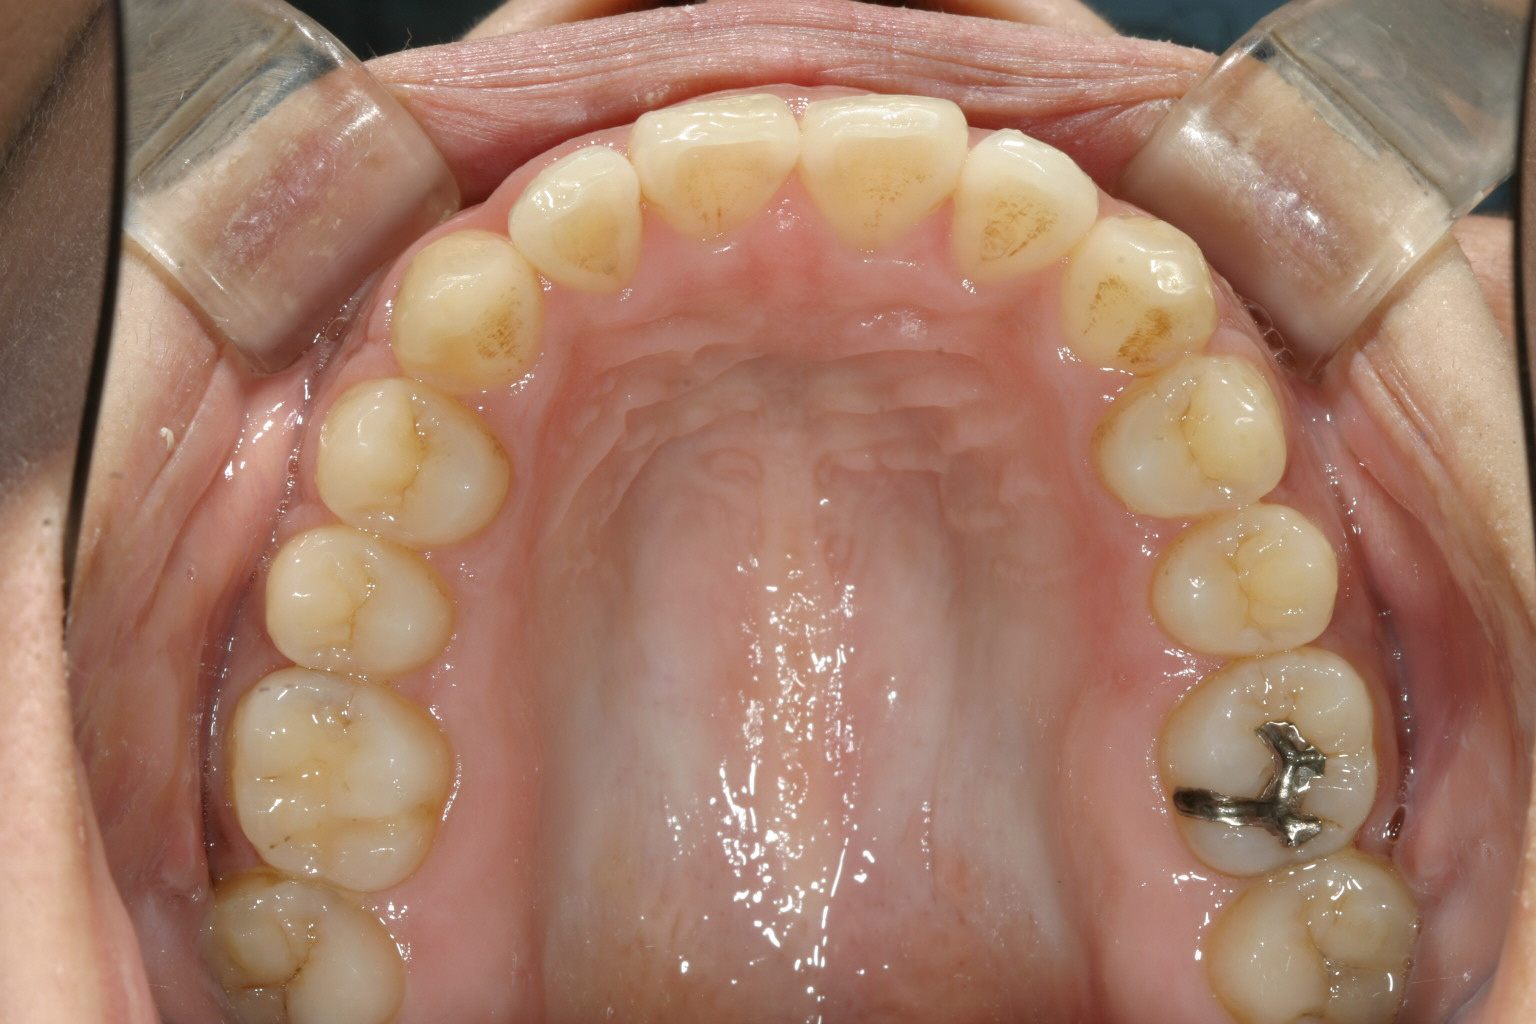

前歯が飛び出して少し翼状捻転しています。

下顎は少しの叢生です。